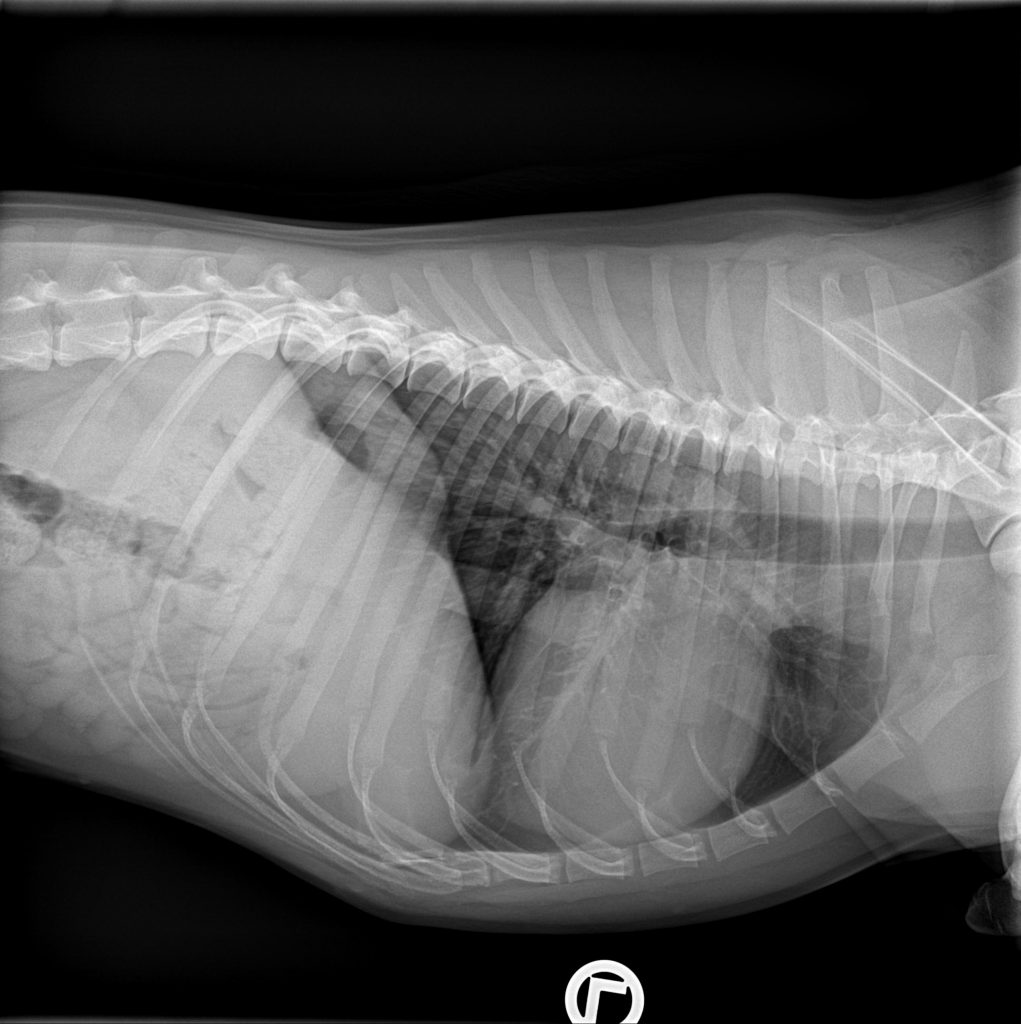

Fortbildungen Kardiologie